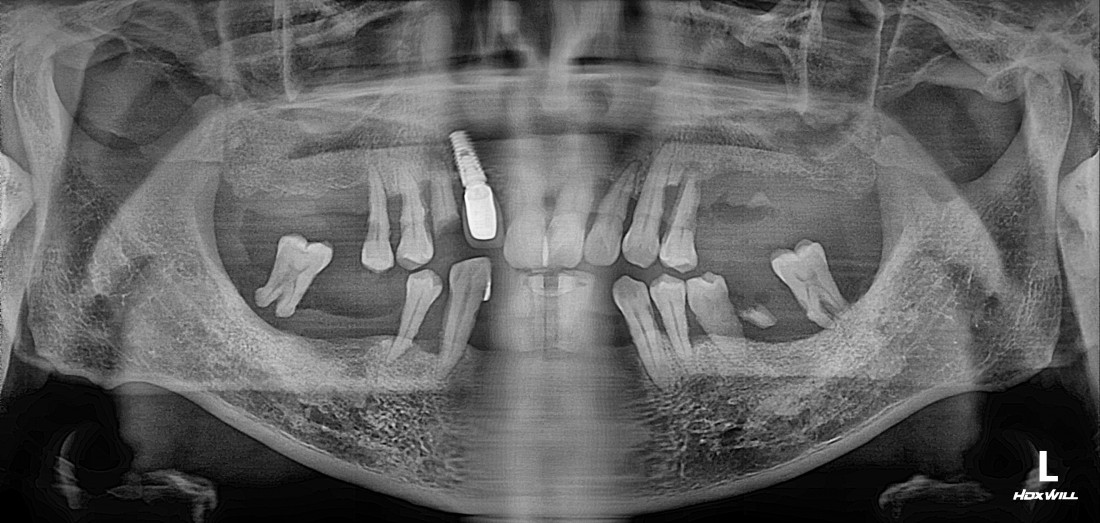

광주 전체임플란트 치과는

디지털가이드 임플란트 방식으로

한 번에 8개 이상의 임플란트를

동시에 식립할 수 있어

단 두 번의 수술만으로 전체임플란트를 완성합니다.

광주 전체임플란트를 생각할 때

임플란트 하나당 가격만 생각하시나요?

저렴한 개당 가격이 중요한 것이 아니고,

최소한의 개수를 식립하여 최대의 효과를 낼 수 있다면

전체 견적이 훨씬 줄어드는 효과가 있습니다.

광주 전체임플란트치과는

대학병원급 최첨단 장비를 갖추고 있으며

디지털 구강스캐너를 활용하여

치아 잇본뜨는 과정을 빠르고 정확하게 합니다.